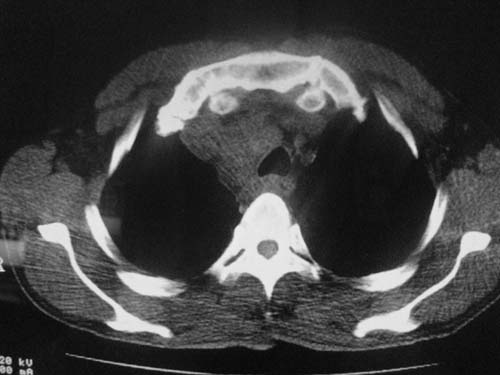

以下是引用科室第一人在2010-3-25 20:30:00的发言:[br]1:纵膈肿瘤性病变,恶性胸腺瘤可能性大伴纵膈右肺门淋巴结转移,右侧胸腔积液。[br]2:右侧肺门肿瘤性病变,纵膈淋巴结转移,右侧胸腔积液。右下叶转移。

以下是引用子期在2010-3-25 21:00:00的发言:[br]先考虑右中央型肺癌伴转移。

以下是引用江广1996在2010-3-25 22:49:00的发言:[br]通常肺癌向纵隔转移多见,纵隔肿瘤向肺内转移少见(有的表现为向肺内侵润)。本例以一元论考虑:右中心型肺癌并纵隔淋巴等多处转移。[br][br][本贴已被 江广1996 于 2010-3-25 22:50:07 修改过]

以下是引用yangyudong333在2010-3-26 6:43:00的发言:[br]“冰冻纵膈”,考虑纵膈淋巴瘤伴肺内及胸膜侵润。